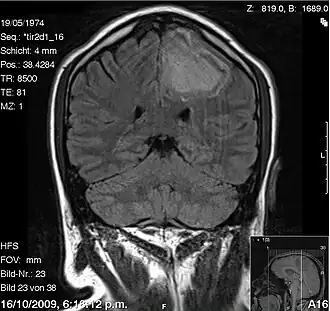

IRM

L'Imagerie par résonance magnétique permet de détecter aussi bien que le scanner l'hémorragie intracérébrale à une phase précoce[7].